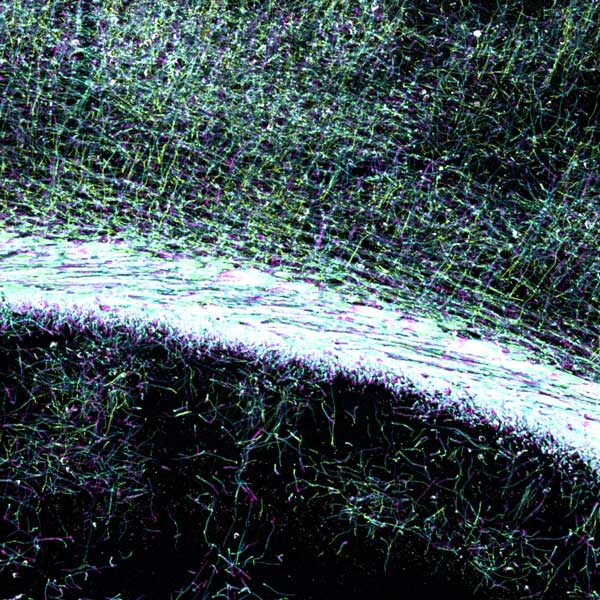

A microscopy showing illuminated myelin in the brain.

Myelin is illuminated in the brain using an antibody for a myelin gene (MBP). Myelin insulates the brain’s neural wiring - axons - ensuring that electrical signals can be properly transmitted.